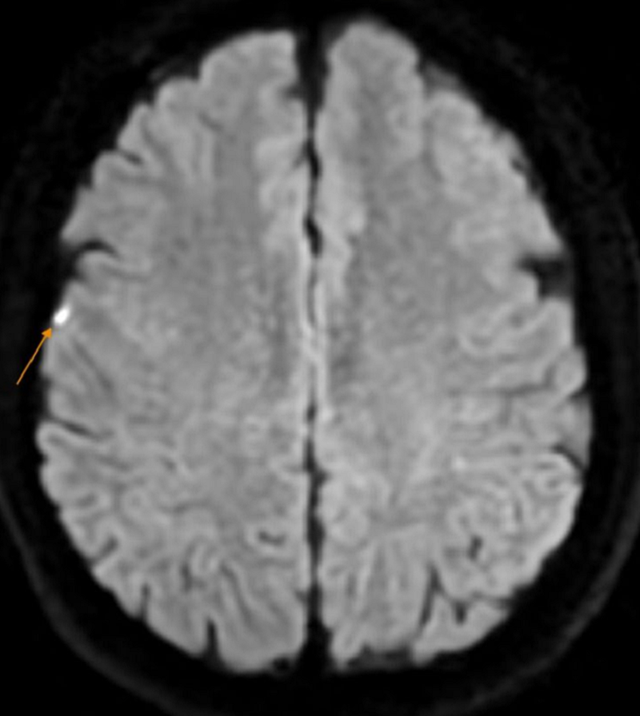

Chụp MRI sọ não ghi nhận hình ảnh tổn thương nhỏ vỏ não vùng đỉnh phải

Để đi đến chẩn đoán xác định, bệnh nhân được chỉ định làm các xét nghiệm cận lâm sàng chuyên sâu, đáng lưu ý kết quả chụp MRI sọ não có hình ảnh tổn thương nhỏ vỏ não vùng đỉnh phải (theo dõi nhồi máu não): Thoái hóa myelin chất trắng dưới vỏ bán cầu đại não và quanh não thất bên hai bên (phân loại Fazekas độ 1); Thiểu sản động mạch não trước bên trái đoạn A1; Viêm xoang sàng hai bên.